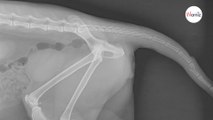

Le vétérinaire fait passer des radios à un chat : quand il voit les clichés il sait que la police doit s’en mêler